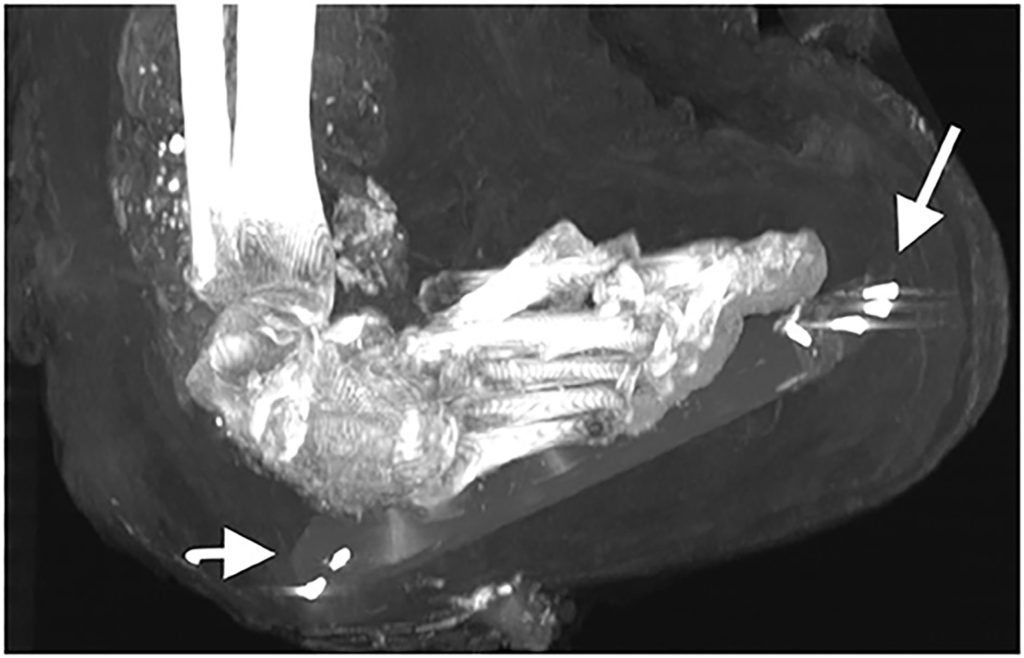

Computed tomography (CT) technology, which creates a cross-section of a body using X-rays, revealed the pharaoh’s face and a chest full of treasure, including 30 amulets and “a unique golden girdle with gold beads,” study co-author Sahar Saleem said in a statement. The findings were published Tuesday in the journal Frontiers in Medicine.

Zahi Hawass, Egypt’s former minister of antiquities and a co-author of the study, told Live Science that the bedazzled girdle may hold “a magical meaning,” while each of the 30 amulets “had a function to help the deceased king in the afterlife.”